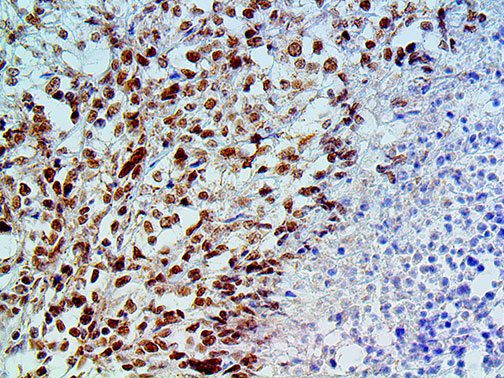

It is the ICU physician who is most likely to witness one of the deadliest manifestations of the abnormal immunological response, the cytokine storm syndrome (CSS). This response is also referred to by some as the cytokine release syndrome (CRS). CSS is characterized by continuous activation and expansion of macrophage and lymphocyte populations, which secrete large amounts of cytokines, causing the cytokine storm. This massive cytokine release is akin to hemophagocytic lymphohistiocytosis (HLH) disease, a syndrome characterized by initial unchecked and persistent activation of cytotoxic T lymphocytes and NK cells.

Clinical and laboratory manifestations of HLH include fever, enlarged liver and/or spleen, neurologic dysfunction, coagulopathy, liver dysfunction, cytopenias (i.e., low levels of erythrocytes, leukocytes, and/or platelets), hypertriglyceridemia, hyperferritinemia, hemophagocytosis, and eventually diminished NK cell activity as the immune system becomes progressively paralyzed. HLH can be familial (primary HLH) or secondary to another disease process (sHLH), such as rheumatic disease, in which it is referred to as macrophage activation syndrome (MAS, characterized by elevated ferritin).

This activation induces inflammatory monocytes to highly express IL-6, starting a localized and then systemic cascade effect that results in hyperproduction of IL-6, which accelerates the inflammatory process. Because IL-6 also increases vascular permeability, excessive levels cause blood vessels to become very leaky. This, along with clotting factors released from vascular endothelial cells, stimulates the coagulation cascade, resulting in microthrombosis (tiny clots), which leads to ischemia and tissue death of the kidney, intestines, heart, liver, brain and extremities.